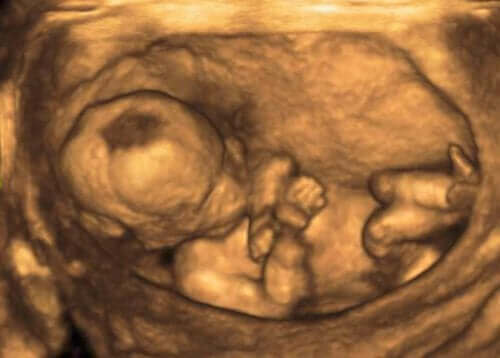

Raskauden aikana suoritettavat lapsiveden tutkimukset voivat paljastaa mahdolliset synnynnäiset häiriöt. Nämä voidaan todeta esimerkiksi lapsivesipunktion eli amniosenteesin avulla.